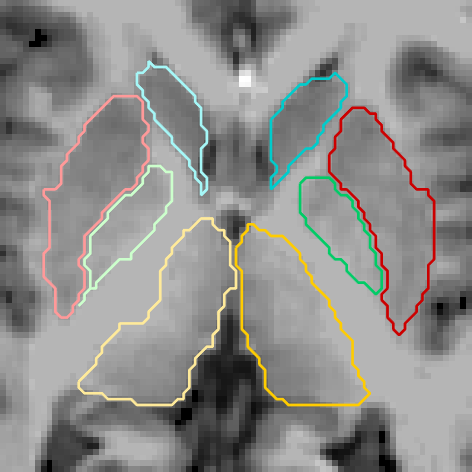

Figures 6 and 3.2 give visual examples of segmentations obtained by our 3D FCNN architecture and standard references contoured by FreeSurfer.

It can be observed that the segmentations generated by our proposed architecture are significantly smoother than those of FreeSurfer, regardless of the subject group (i.e diagnosis, age, site employed or not in training). We also notice that our system is better at identifying thin regions in the structures of interest, for instance, the lower extremities of pallidum (green regions).

Site used in training

FreeSurfer Refer to caption Our CNN Refer to caption Refer to caption Refer to caption

Refer to caption Refer to caption

Figure 6: Visual examples of our 3D FCNN architecture compared with the standard references contoured by FreeSurfer, for three test subjects from sites used in training.